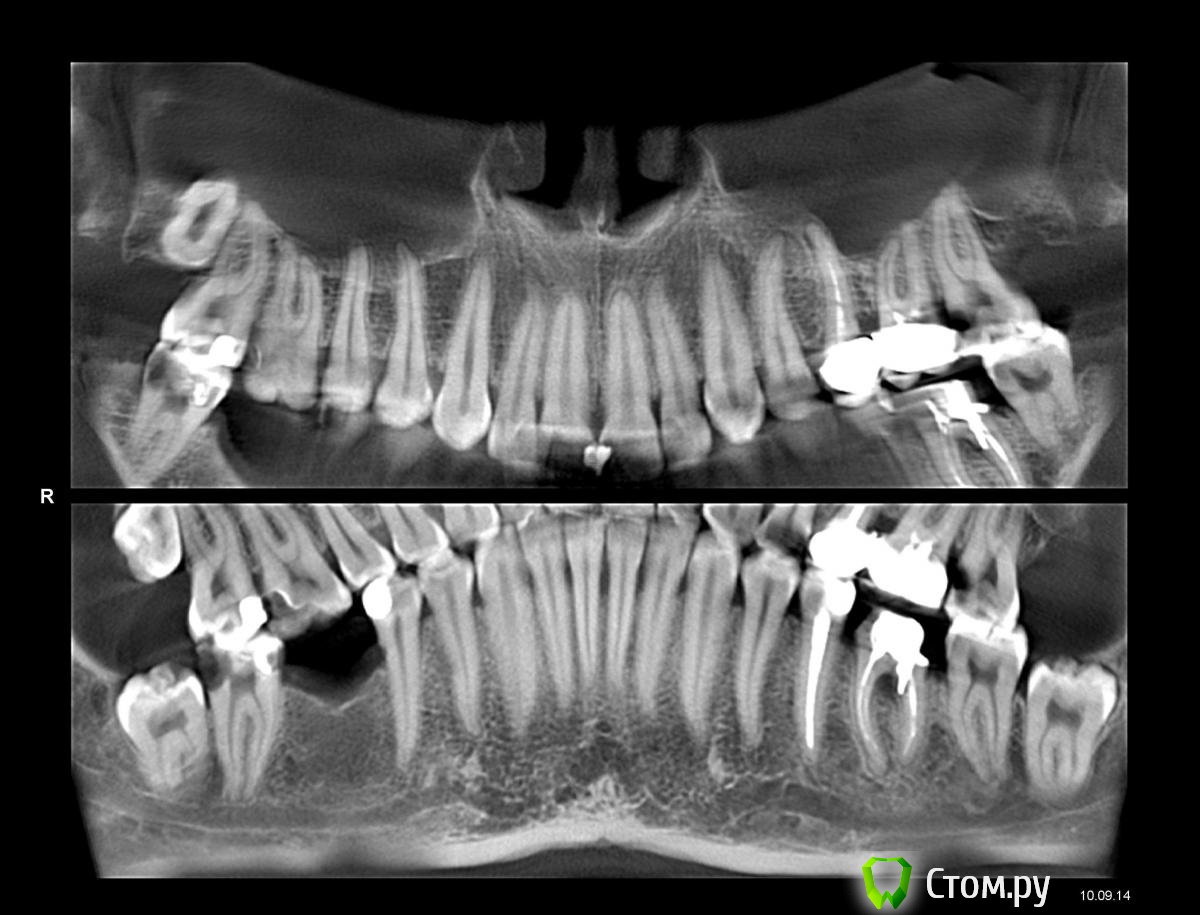

Jonatan Опубликовано 16 сентября, 2014 Поделиться Опубликовано 16 сентября, 2014 Здравствуйте!Всегда боялась лечить зубы, а после того, как рекомендованный терапевт пробил корень арматурой, зуб под удаление(а полугодом раньше другой врач поставил большую пломбу даже без штифтов - так что зуб довольно быстро начал откалываться)-совсем забуксовала в поисках хорошего врача.Досняла ОПТГ и теперь консультируюсь и уже начала лечить (в стом. №4 в Москве - по отзывам и уже от безысходности, в-общем-то)правую нижнюю 7-ку из-за развившегося пульпита и боли.Проблемы:1). После закладки девитализирующей (с мышьяком?) пасты 13.09 через 3 дня, т.е. 16.09, зуб начал болеть при настукивании.17.09 рано утром 2-й этап (депульпирование и лечение каналов), но я прочитала, что это плохо, когда зуб болит таким образом .1а). Кроме того, при рассверливании зуба под заморозкой (ожидание 10 минут) было больно, зато спустя полчасавсе замерзло так (от скулы до ключиц), что отошло только через 5 часов. Странно, раньше я ничего не чувствовалапри первичном, перед мышьяком, депульпировании под заморозкой, но отходило быстрее, у меня обычная чувствительность.1б). Есть какие-то стандарты стом. гигиены, на которые надо обращать внимание? Муж меня пугает какими-то одноразовыми сверлами,спидом-гепатитом, а я привыкла лечиться в обычной поликлинике и никогда не обращала внимание на то, что врач делает вне поля зрения.Хотя в последний раз в районной поликлинике врач, сделавший перфорацию, смутил меня протиркой окровавленных инструментов ваткой со спиртом.2). На общей консультации мне прописали лечение ПУЛЬПИТА 5-ти зубов (все 7-ки и 6-ка вверху).Нет ли способа сохранить зубы частично живыми, если боли еще нет? Или депульпировать и чистить каналы нужно на всех указанных зубах?3). На общей консультации врач сказал примерно так: "импланты - глупости, вам абсолютно показаны мосты" (потому что зубы по бокам от уже удаленной и той, что нужно удалять из-за перфорации корня районным стоматологом, шестерок лечены). Соотв. его стратегия лечения - подготовка зубов под мосты.Я же при прочих равных и отсутствии тотальных противопоказаний хочу поставить вкладки-коронки на все депульпированные зубы и импланты нижних 6-к -мосты мне кажутся сомнительным решением в моем случае и по долговременности, и по распределению нагрузок.Однако большая потеря кости справа, воспаление зоны перфорации слева - тоже проблемы.Если врач прав, предлагая мосты, как улучшить прогноз продолжительности жизни мостов?Культевые вкладки врач не предложил, под мостом будут штифты в пломбе...Уважаемые специалисты, прокомментируйте, пожалуйста! Ссылка на комментарий